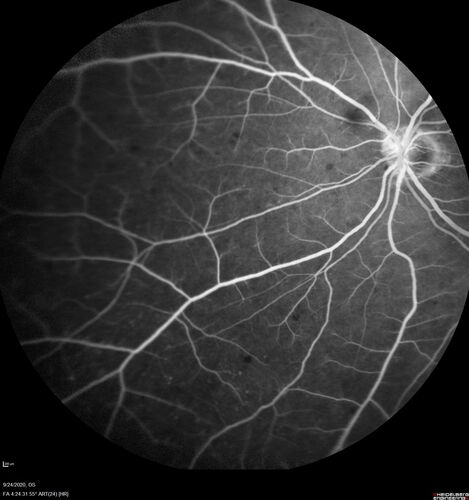

Elevated Episcleral Venous Pressure and Retinal Hemorrhages in both eyes

78 year old female with chronic red eye.   The eyes are red all the time now.  She is on Xeralto because of a history of blood clots in her lungs (2005 about).  She has not had problems since.  She has had floaters for many years.  Ever since her eyes got funny she sees more floaters in both eyes.  She had a brain scan over 6 months ago which was OK.  She also had double vision when this first started which went away.  She could not drive for a few months.

VA OD: Dcc20/32-1

VA OS: Dcc20/125

IOP: TP: OD:17 OS:16

Neuroimaging did not show a CC fistula